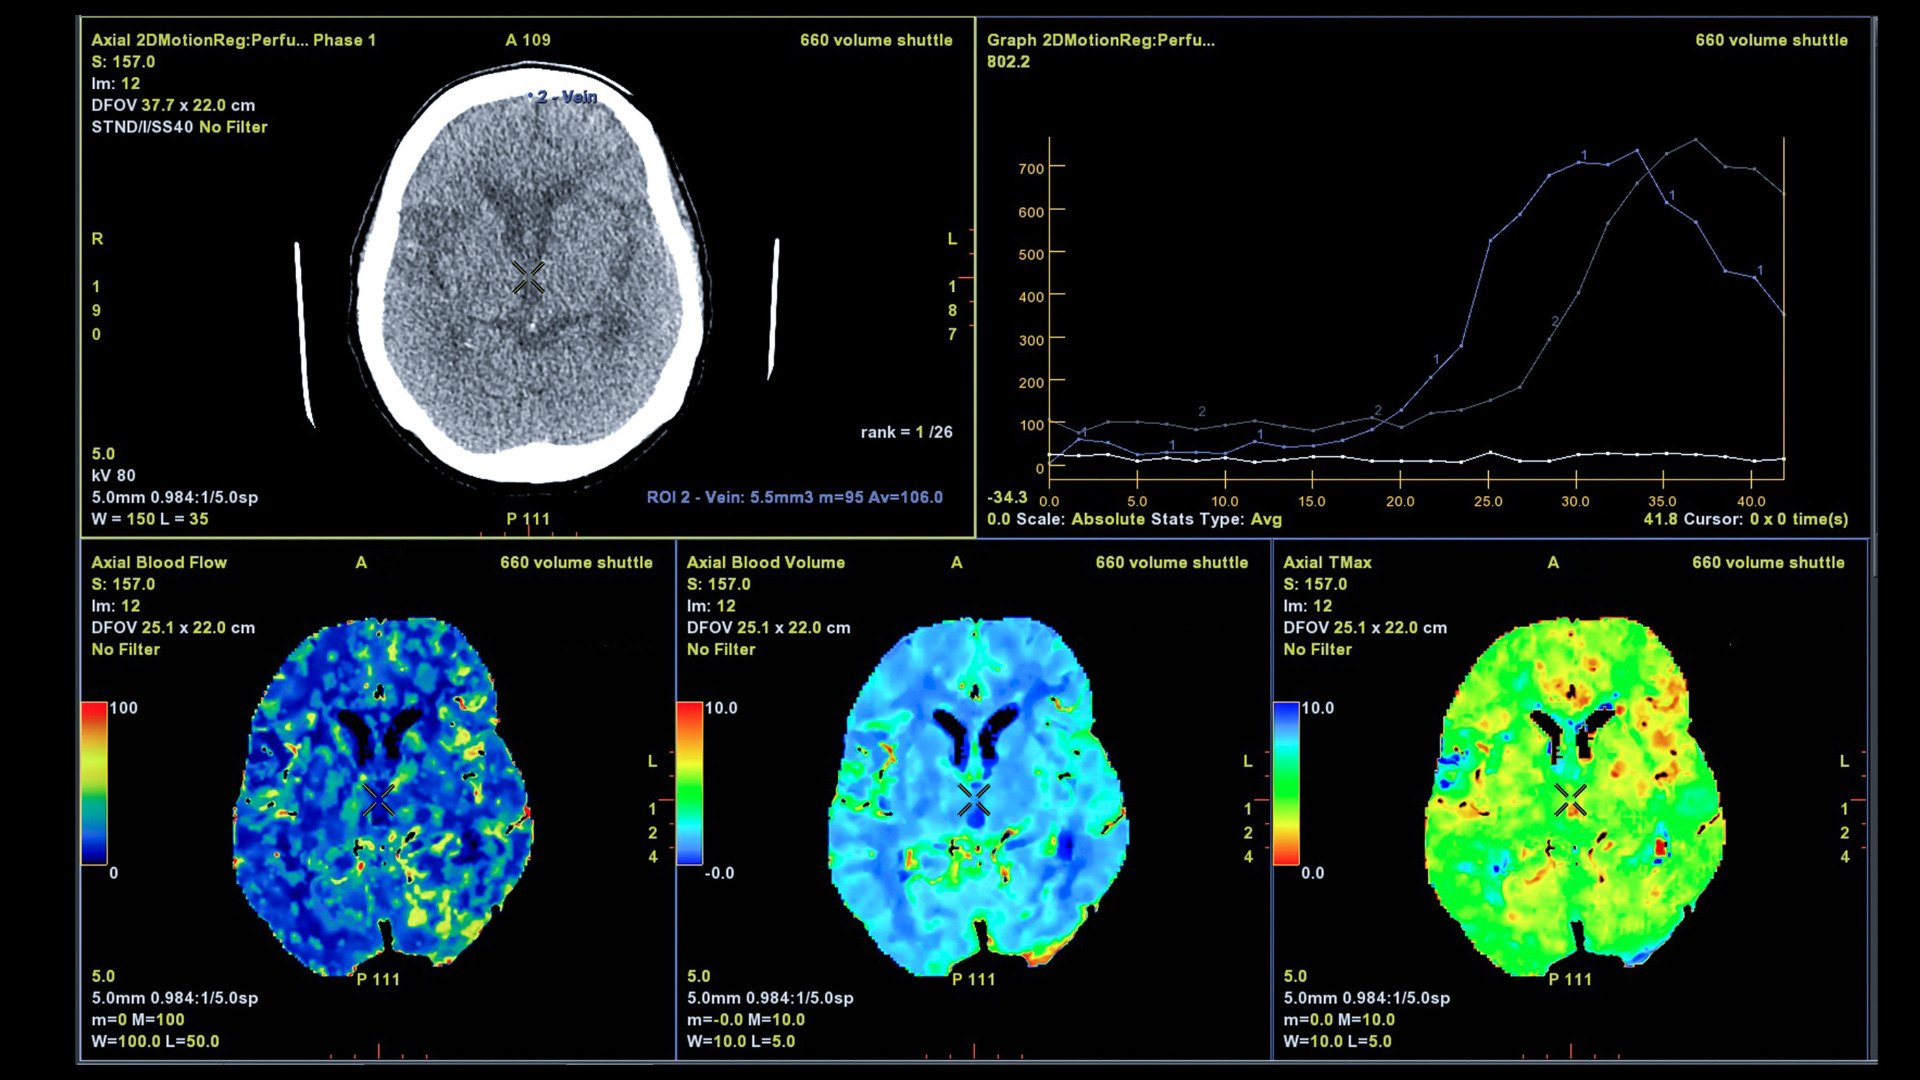

Chụp CT (chụp cắt lớp vi tính): Chụp CT giúp bác sĩ xem xét tình trạng máu rỉ trong não bộ. Kỹ thuật này sử dụng tia bức xạ X để tạo ra hình ảnh một mặt cắt ngang hoặc tạo ra hình ảnh chi tiết về lưu lượng máu trong động mạch não. Kỹ thuật chẩn đoán hình ảnh này sẽ thể hiện kích thước, vị trí và hình dạng của túi phình động mạch não.

Chụp MRI (chụp cộng hưởng từ): Kỹ thuật này sử dụng sóng vô tuyến để tạo ra hình ảnh chi tiết về động mạch não và có thể hiển thị kích thước, vị trí và hình dạng của túi phình động mạch.

Chụp động mạch não bằng máy DSA: Đây là một kỹ thuật can thiệp nội mạch với mục đích thu thập hình ảnh động mạch não. Kỹ thuật này sẽ giúp bác sĩ phát hiện những tắc nghẽn, xác định điểm yếu trong thành động mạch não, trong đó có túi phình mạch não.

Phân tích dịch não tủy (CSF): Bác sĩ sẽ thu thập mẫu dịch não tủy bằng cách chọc dò tủy sống, được bác sĩ chỉ định với mục đích đo chất lỏng bao quanh và bảo vệ não, tủy sống. Thủ thuật phân tích dịch não tủy sẽ giúp bác sĩ phát hiện vấn đề chảy máu xung quanh não.